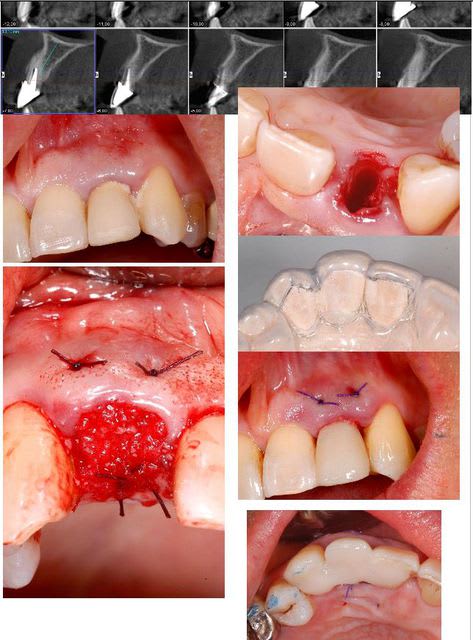

tu peux aussi faire ça;

glisser et interposer une membrane entre la parois vestibulaire osseuse et le périoste que tu décolles en partant de l'alvéole et en restant en contact osseux...

Le classique "Ice Cream Cone Technic"

Avec une telle gencive, ça va.